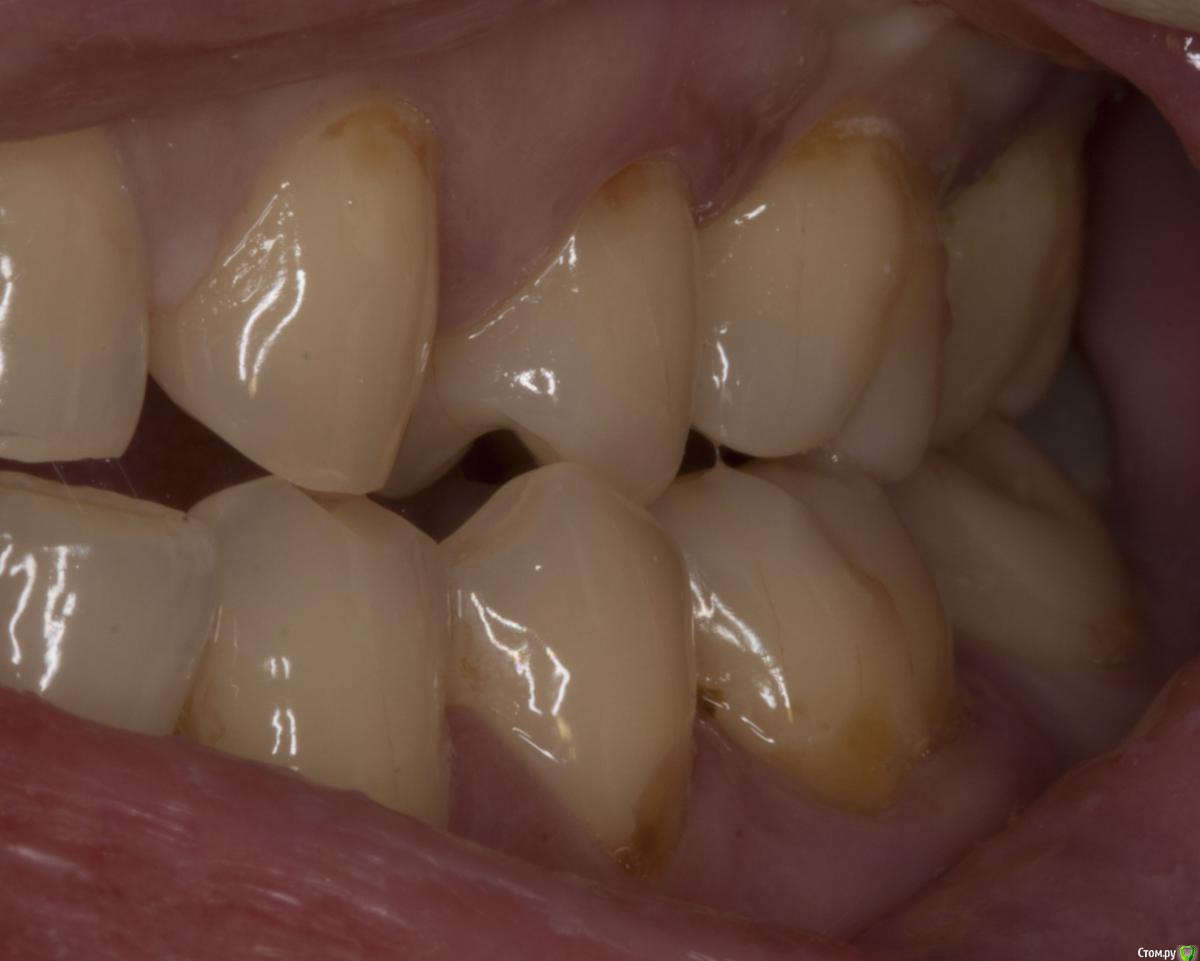

M@estro Опубликовано 29 июля, 2015 Поделиться Опубликовано 29 июля, 2015 (изменено) Травматический узел. Изменено 29 июля, 2015 пользователем M@estro 10 Ссылка на комментарий

M@estro Опубликовано 3 августа, 2015 Поделиться Опубликовано 3 августа, 2015 но у вашем случае у антагониста пломба, а у паца тс нет пломбы на антагонисте. или там другая причина супраоклюзии? Я специально сделал серию фото, чтобы виден был перегруз 2.6 при левой латеротрузии. Ссылка на комментарий

diesel87 Опубликовано 4 августа, 2015 Поделиться Опубликовано 4 августа, 2015 Я специально сделал серию фото, чтобы виден был перегруз 2.6 при левой латеротрузии. как бороться с этим на ранних стадиях? Ссылка на комментарий

brg Опубликовано 9 августа, 2015 Поделиться Опубликовано 9 августа, 2015 как бороться с этим на ранних стадиях?Пришлифовывать, убирать сверх нагрузку. Ссылка на комментарий

M@estro Опубликовано 9 августа, 2015 Поделиться Опубликовано 9 августа, 2015 как бороться с этим на ранних стадиях? 1) Ортодонтия 2) Избирательное пришлифовывание Ссылка на комментарий